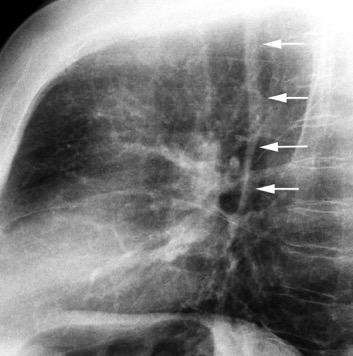

102. HEMATOMA MEDIASTÍNICO.

Hematoma retroesternal y pericárdico en cirugía de válvula mitral. Migración de suturas